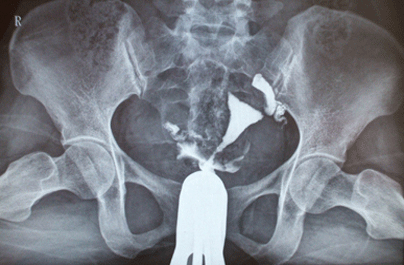

输卵管造影是用来检查女性输卵管通畅与否的一种检测方法。输卵管造影是临床上应用较为广泛的方法之一。经X线的子宫输卵管造影是通过导管向宫腔及输卵管注入造影剂,利用X线诊断仪行X线透视及摄片,根据造影剂在输卵管及盆腔内的显影情况来了解输卵管是否通畅、阻塞部位及宫腔形态的一种检查方法。

该检查损伤小,在有经验的医验操作下,并附以数字X光机的应用,能对输卵管堵塞作出正确诊断,准确率达98%,且具有一定的治疗作用,是用来了解输卵管是否通畅及通畅的程度和具体堵塞部位的最常用的检查方法。在许多方面是超声、CT、核磁、宫腔镜、腹腔镜、输卵管镜等所无法替代的。